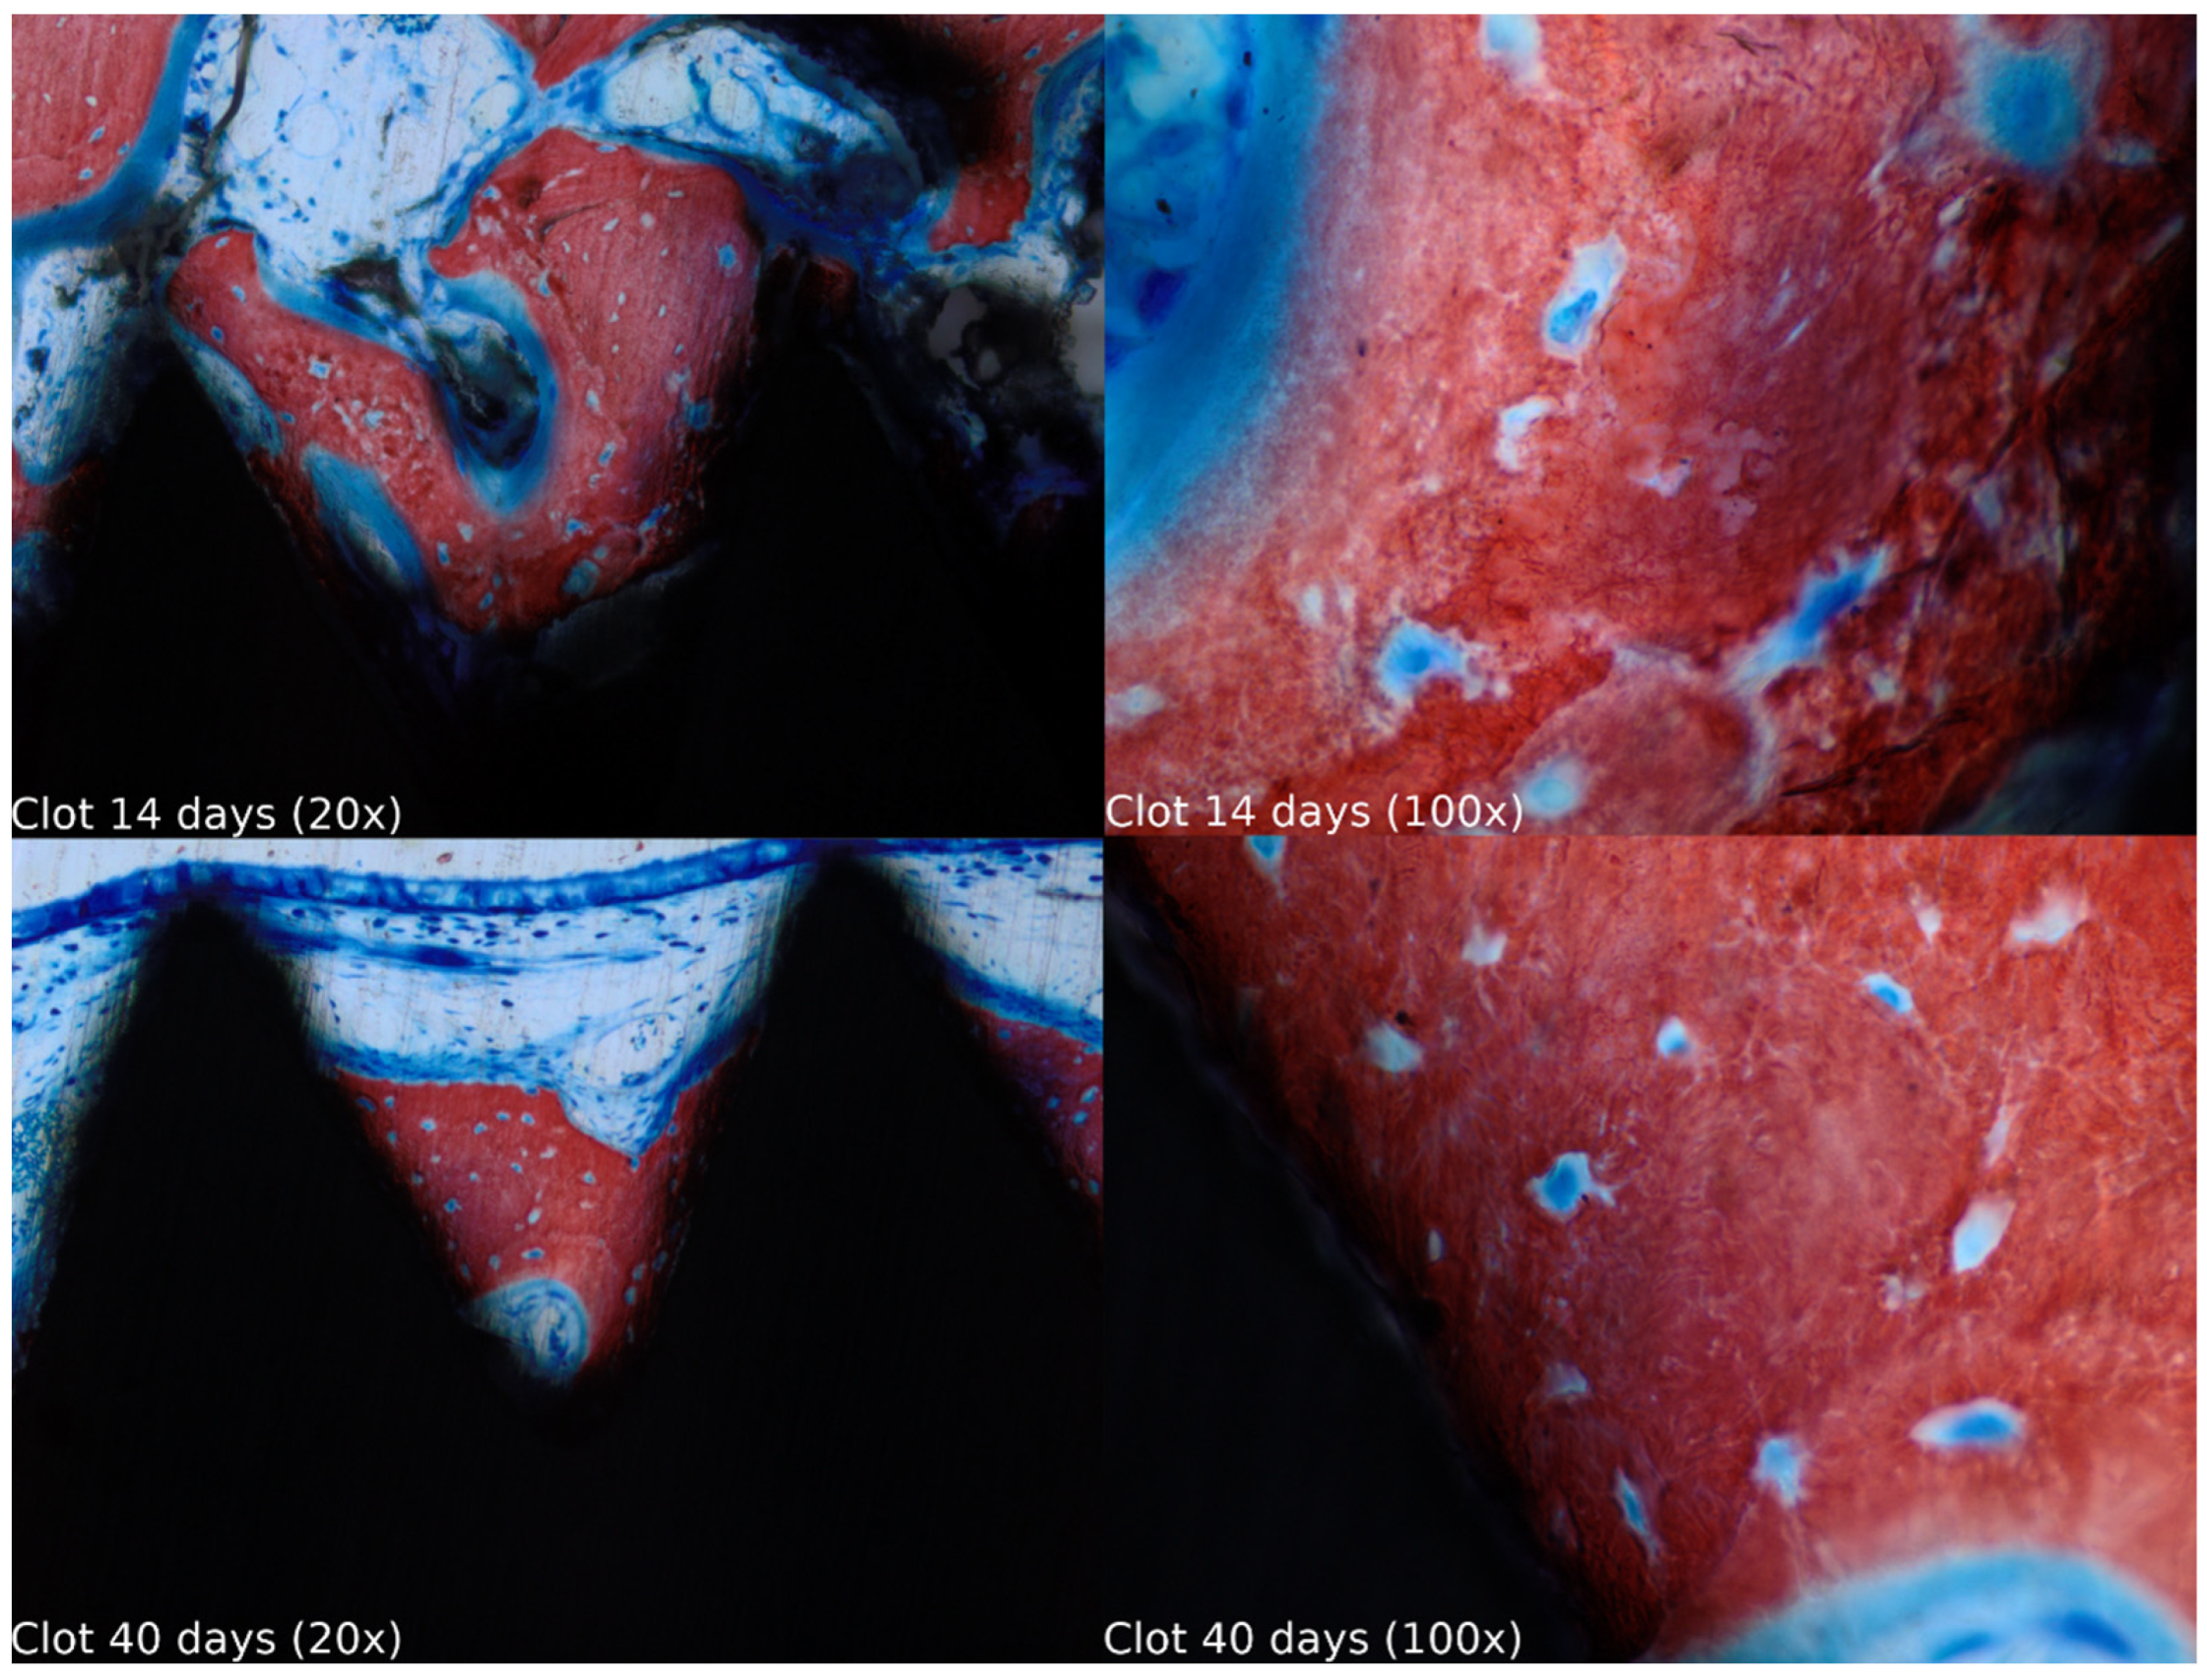

3.1. Descriptive Histology (n = 40)